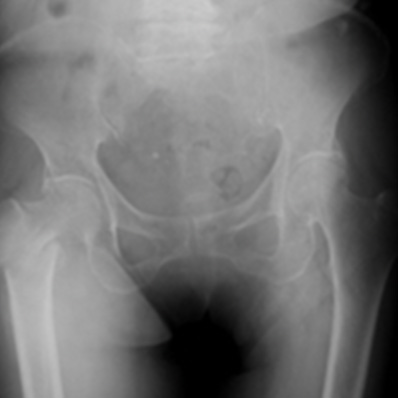

股関節脱臼骨折

大腿骨転子部骨折